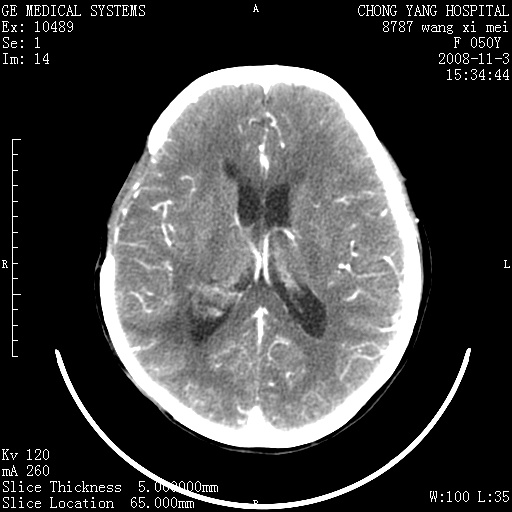

右侧颞顶部可见低密度实变影,内见不规则钙化灶,边界不清,占位效应明显,侧脑室后角受压移位,符合胶质瘤术后复发改变。

右颞骨局限性缺如,局部脑组织无外隆。右颞叶可见片状脑脊液样低密度影,边缘较清,右侧侧脑室三角区可见一块状等密度影,且伴有强化,余未见明显异常改变。

考虑:右大脑术后改变伴肿瘤复发。

手术后局部片状低密度改变(软化灶),其后方颞叶似等密度病灶,界限不清,内见钙化,有轻度占位效应,但增强后强化之血管走行如常。应不考虑:复发!

应考虑肿瘤复发,右颞顶叶已出现轻度强化肿块.必要时可与原片比较以下.

右侧颞顶部混杂密度影,内有钙化,有占位效应。应该是复发灶。结合术后片更好。